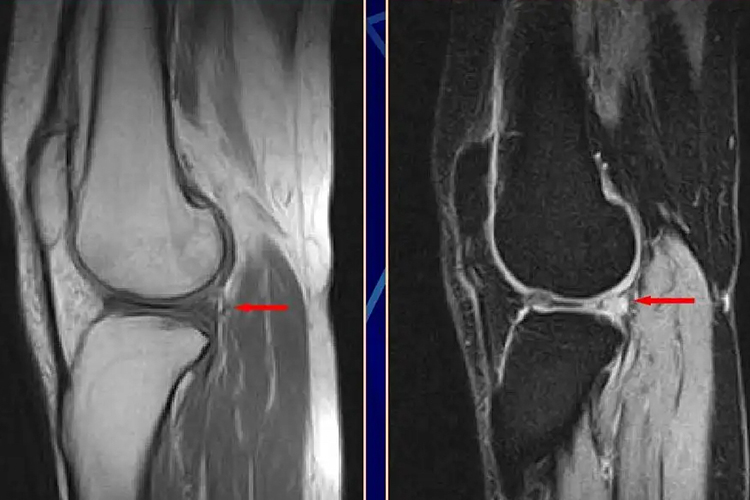

半月板内侧后角撕裂的常见表现为膝关节剧痛、肿胀、无法伸直,还会导致半月板不稳定,出现移位,发病与自身老化相关。

半月板内侧后角撕裂的临床表现为局限性疼痛、关节肿胀、无法伸直,以及绞锁与弹响、股四头肌萎缩、半月板部位有压痛等。此外,还会导致半月板不稳定,出现移位等情况。